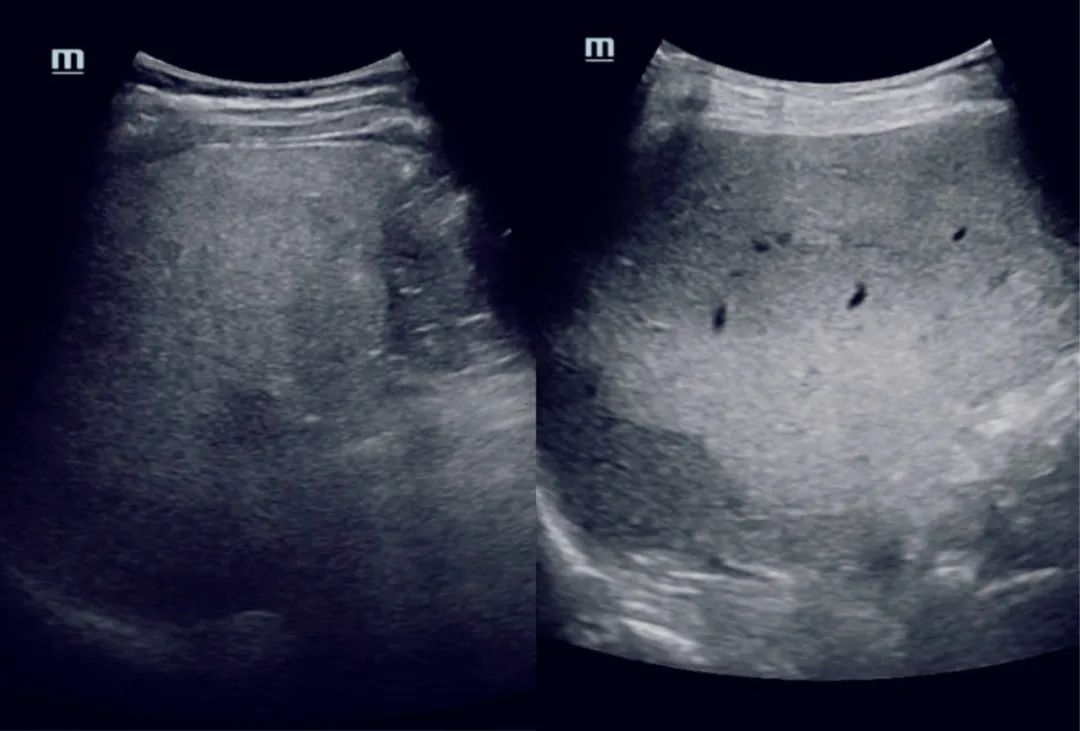

【超声检查】

因其无放射性损创、质优价廉,可实时动态显示受检组织器官,可重复检查,孕产妇及孩童均适用,是在各级医院里均较普及的一种影像学检查方式之一。

常规腹部超声检查可以定性及半定量对脂肪肝的有无及程度进行大致判断分级,适合长期随访观察。